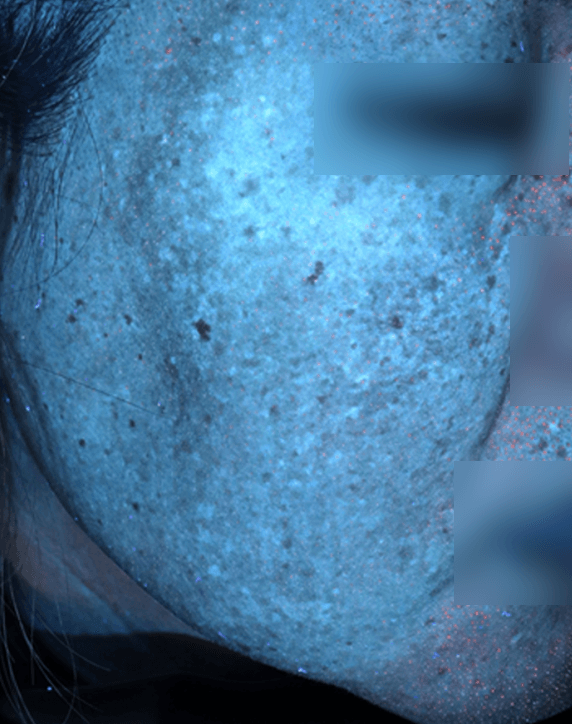

자외선광 1회차 / 10회차

2025.02.24

2025.05.08